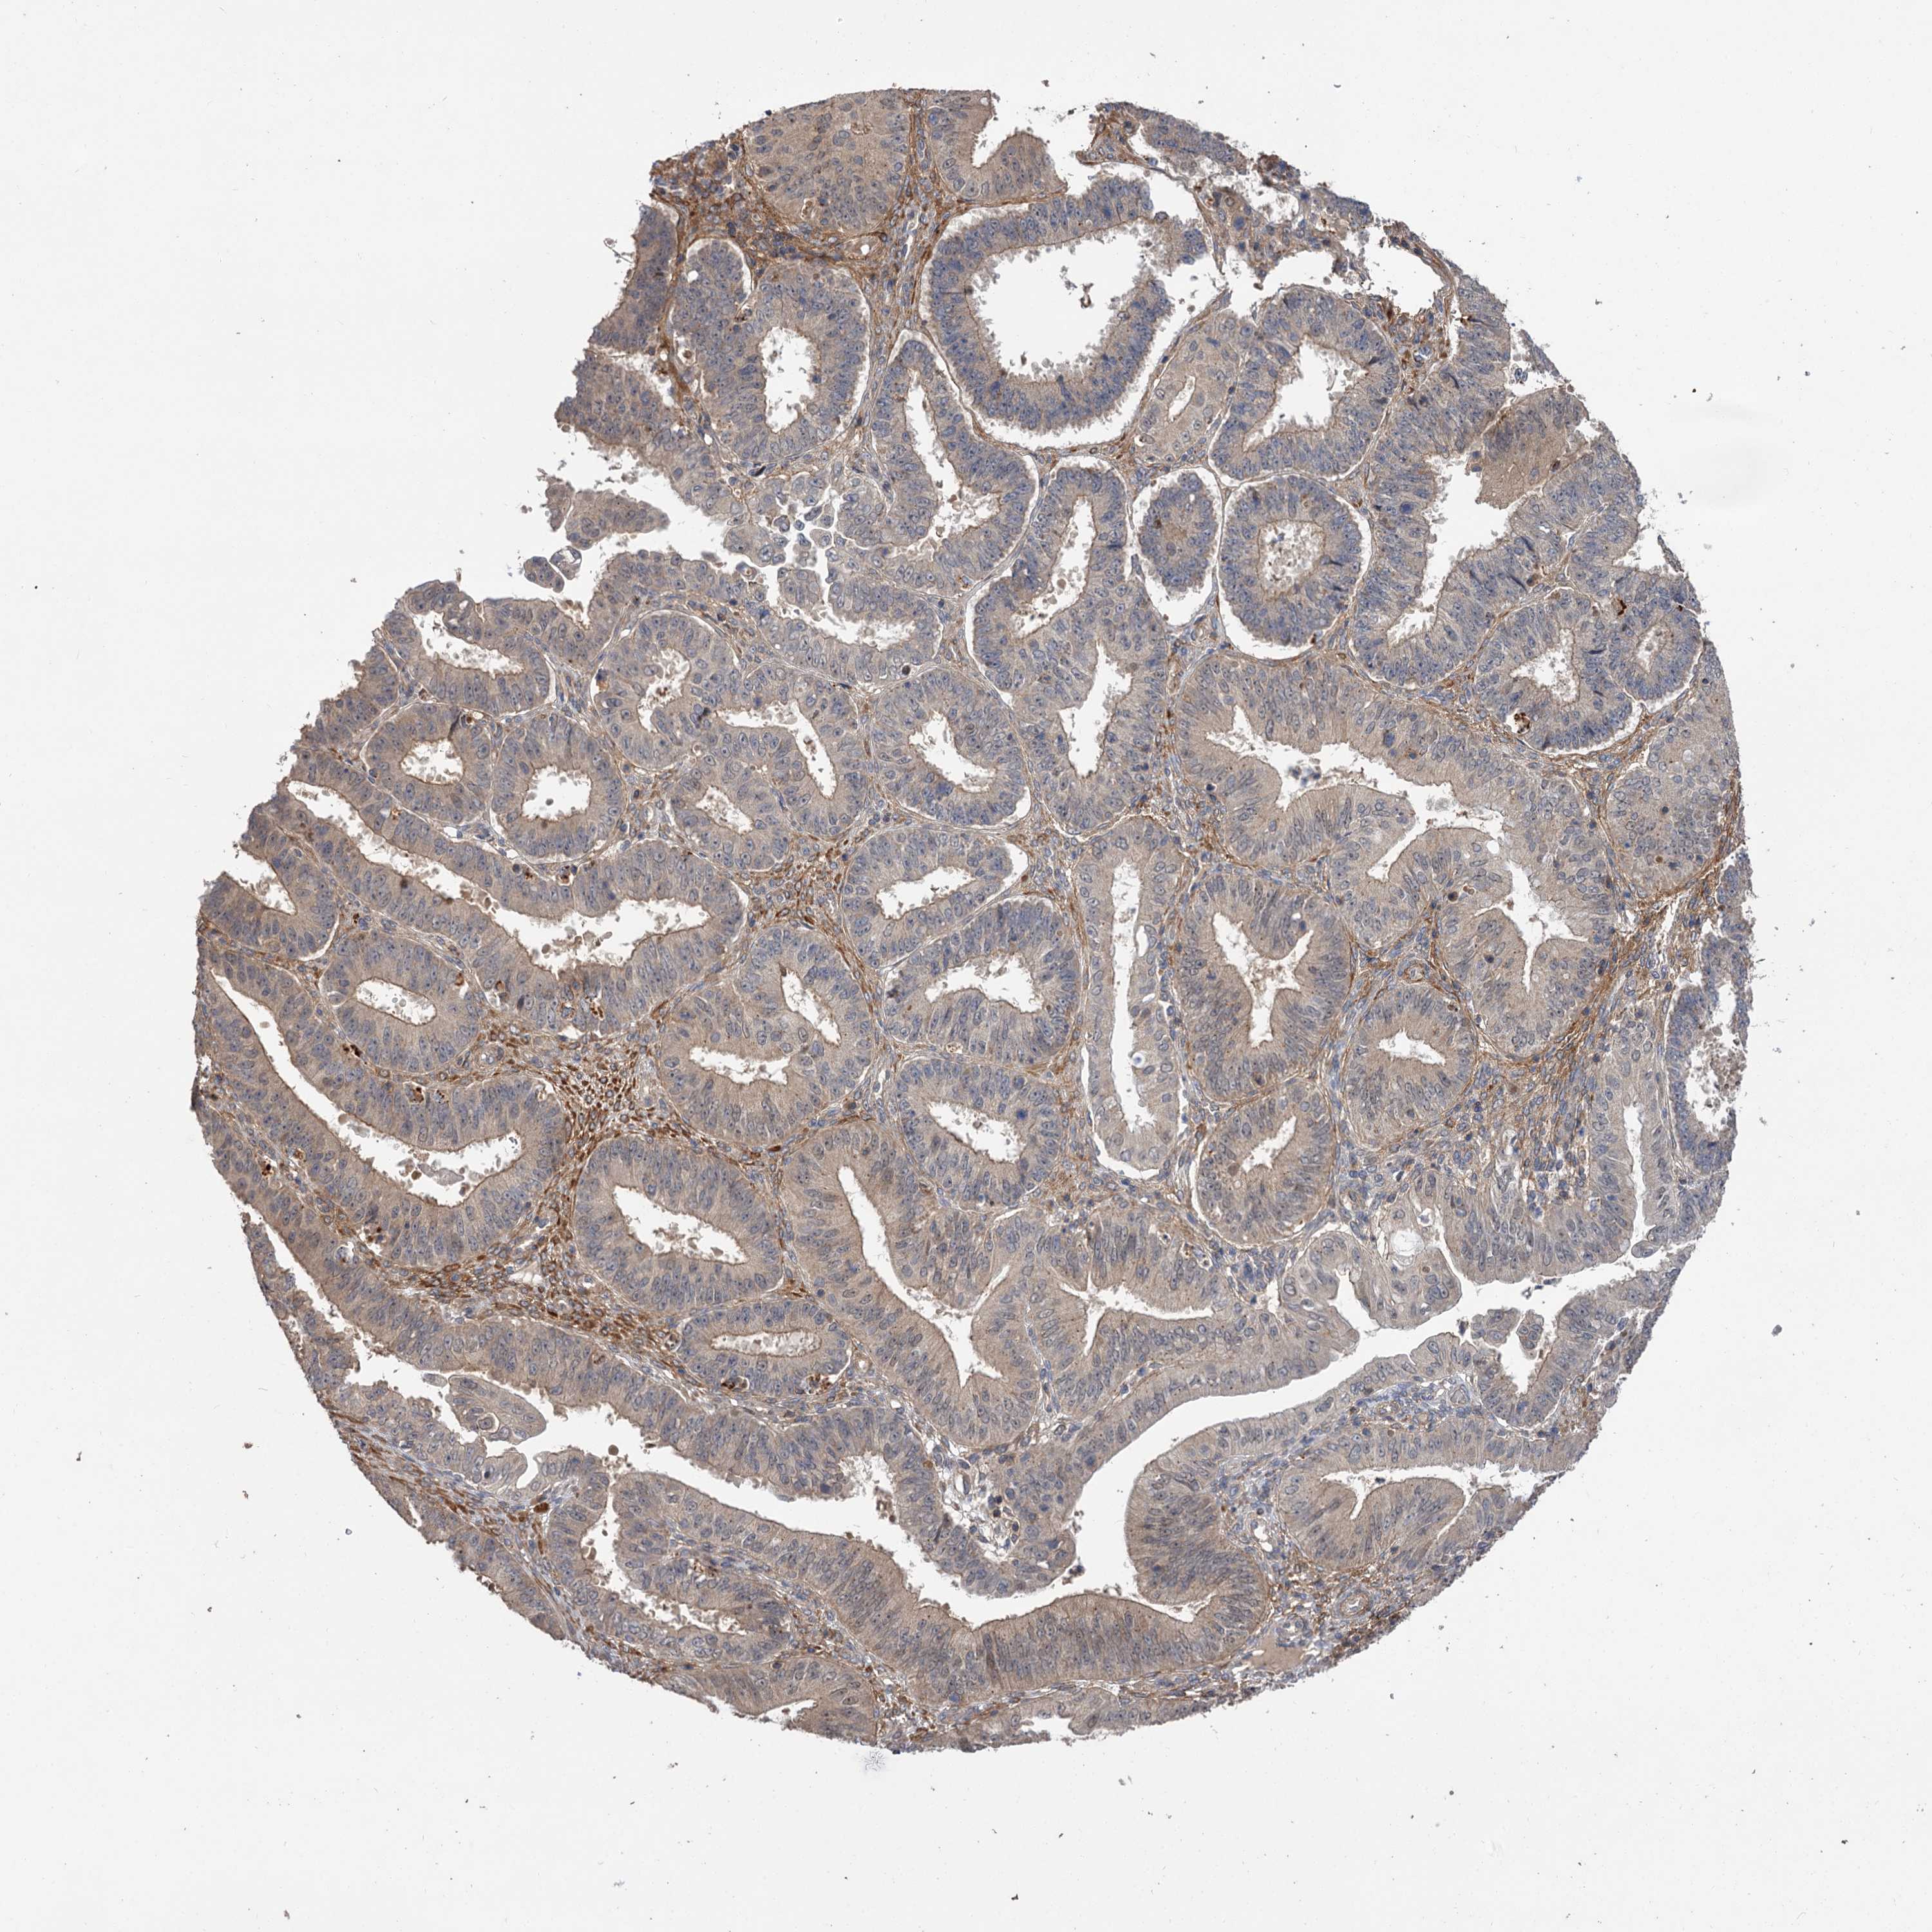

OVARIAN CANCER - Protein expressioni

A mouse-over function shows sample information and annotation data. Click on an image to view it in a full screen mode. Samples can be filtered based on level of antibody staining by selecting one or several of the following categories: high, medium, low and not detected. The assay and annotation is described here.

Note that samples used for immunohistochemistry by the Human Protein Atlas do not correspond to samples in the TCGA dataset.

Antibody stainingi

Antibody staining in the annotated cell types in the current human tissue is reported as not detected, low, medium, or high, based on conventional immunohistochemistry profiling in selected tissues. This score is based on the combination of the staining intensity and fraction of stained cells.

Each image is clickable and will lead to virtual microscopy that enables deeper exploration of all samples and also displays staining intensity scores, fraction scores and subcellular localization as well as patient and tissue information for each sample.

Antibody HPA038850

Antibody HPA038851

Cystadenocarcinoma, serous, NOS

Carcinoma, endometroid

Cystadenocarcinoma, mucinous, NOS

Carcinoma, NOS